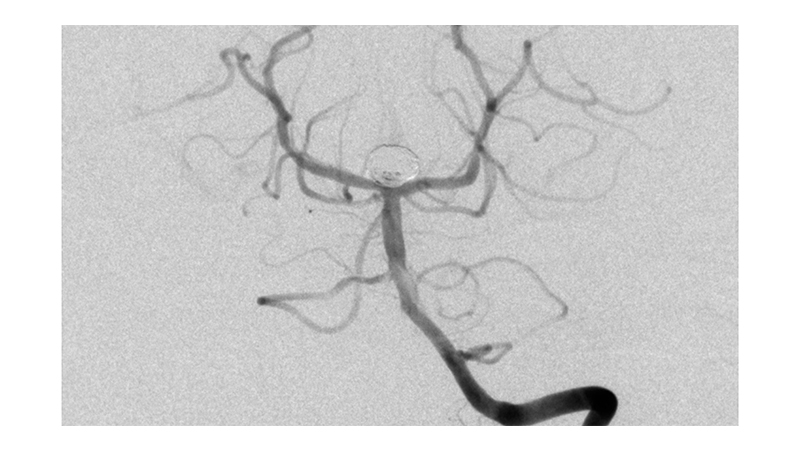

Εικόνα 1 και 2: Ραγέν ανεύρυσμα της κορυφής της βασικής αρτηρίας, το οποίο έχει ευρύτατο αυχένα. Η ασθενής ευρίσκεται ήδη σε φάση προχωρημένου αγγειοσπάσμου. Το ανώτερο τριτημόριο της βασικής αρτηρίας παρουσιάζει σημαντικό σπασμό με ελάττωση της διαμέτρου του.

Ταυτόχρονα τριχοειδική απεικόνιση του Ρ1 και Ρ2 τμήματος των οπισθίων εγκεφαλικών αρτηριών αμφοτερόπλευρα, λόγω έντονου αγγειοσπάσμου.